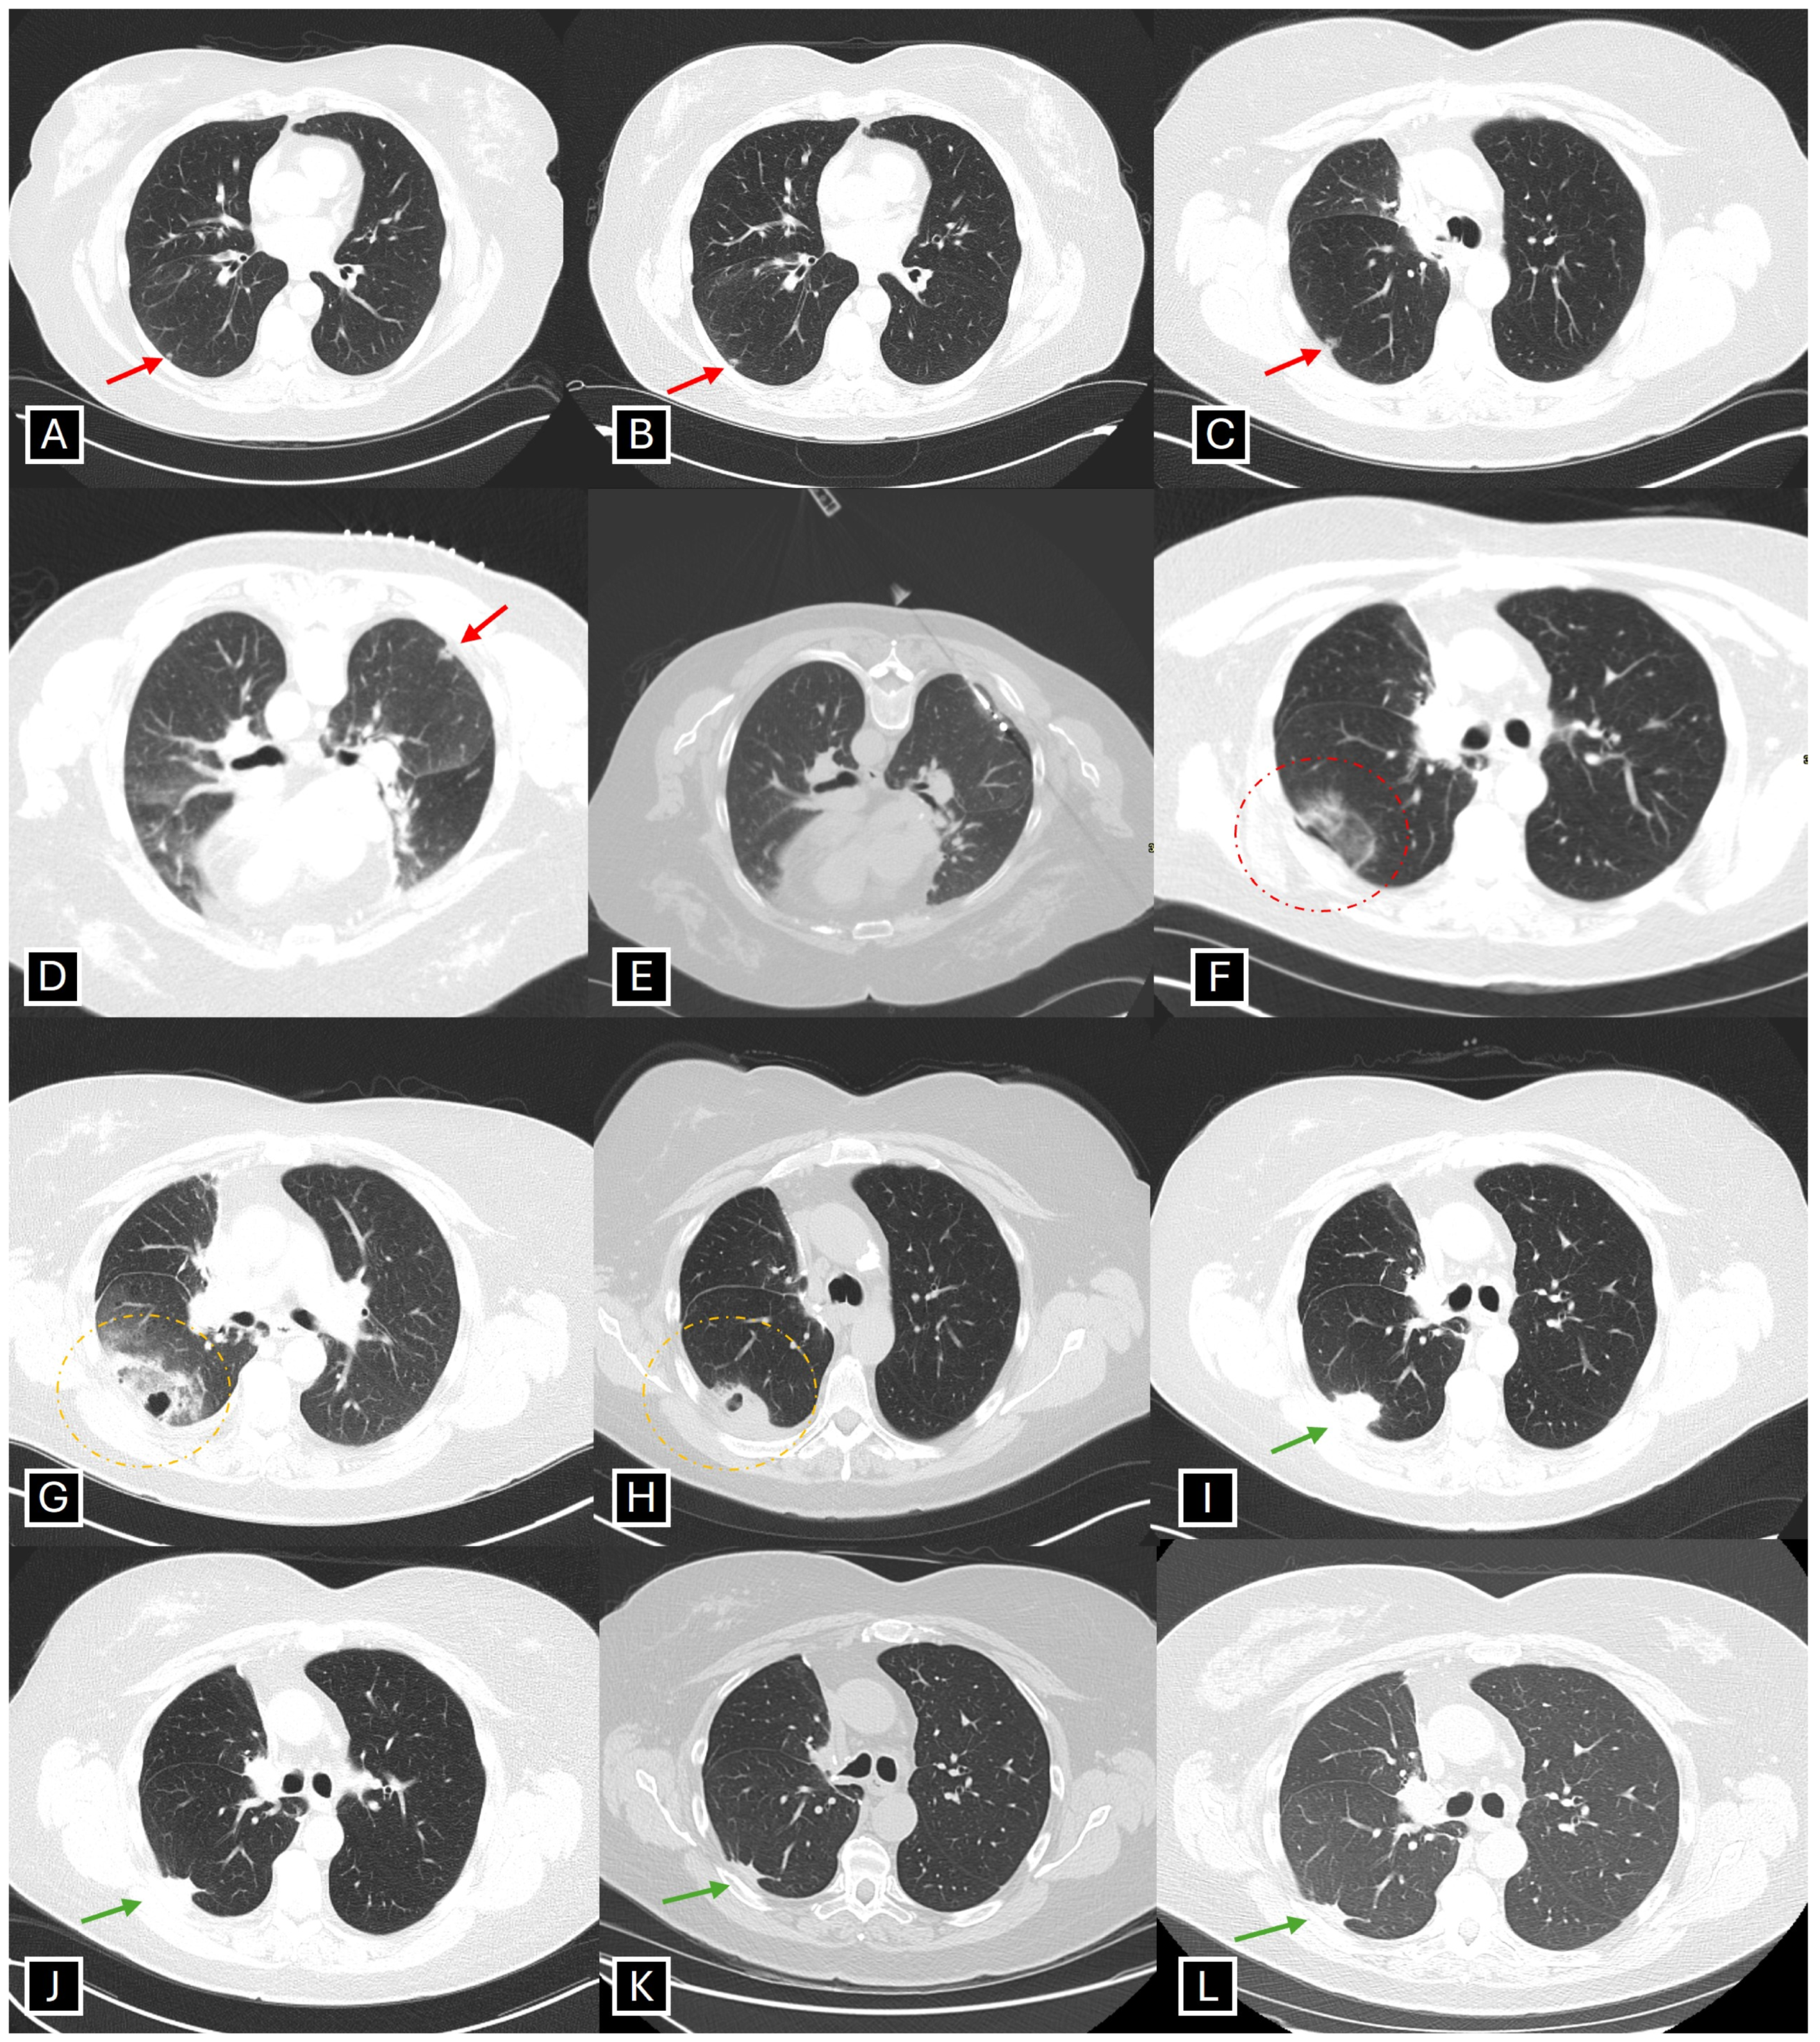

- Paez-Carpio, A.; Gomez, F.M.; Isus Olive, G.; Paredes, P.; Baetens, T.; Carrero, E.; Sánchez, M.; Vollmer, I. Image-guided percutaneous ablation for the treatment of lung malignancies: Current state of the art. Insights Imaging 2021, 12, 57. [Google Scholar] [CrossRef] [PubMed]

- Smith, S.L.; Jennings, P.E. Lung radiofrequency and microwave ablation: A review of indications, techniques and post-procedural imaging appearances. Br. J. Radiol. 2015, 88, 20140598. [Google Scholar] [CrossRef]